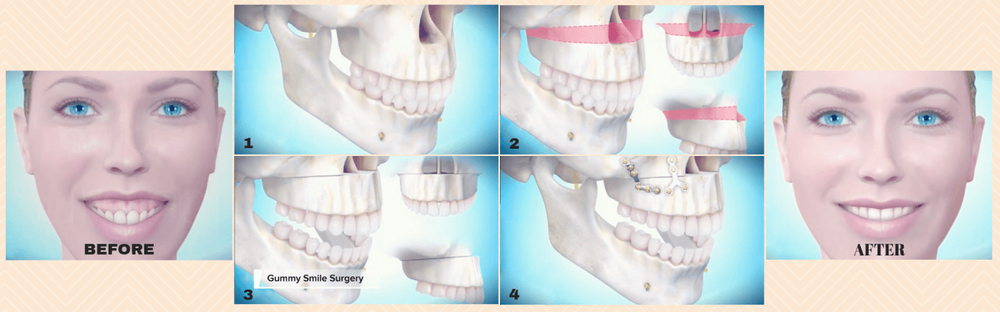

How the surgery look?

Shorter nose and Reversed most of the downward growth

There are cases where the length of the face is simply long, but there are also cases where the mouth cannot be completely closed due to malocclusion or the gums are severely visible when smiling.

How the surgery look?

Shorter nose and Reversed most of the downward growth